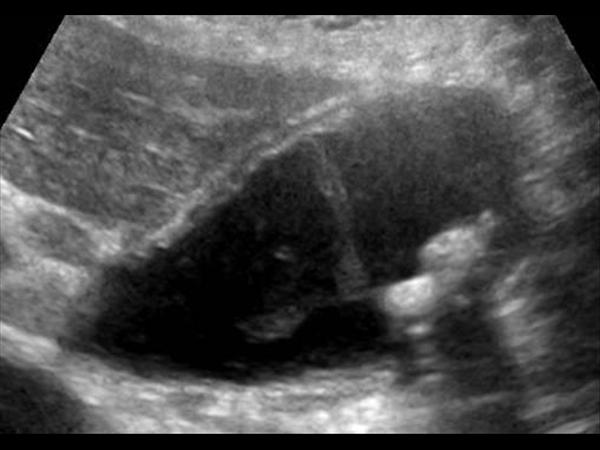

Viêm túi mật

» Thông tin: Nữ giới – 87 tuổi.

» Lâm sàng: Đau mạn sườn phải / Sốt.